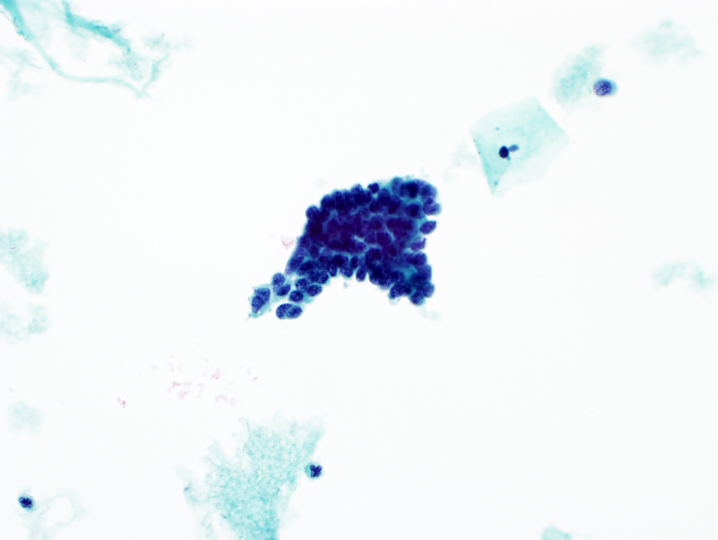

- Atypical endocervical cells, favor neoplastic

- Abnormal cells occur in sheets and strips with nuclear crowding, overlap or pseudostratification

- Rare cell groups with rosettes (gland formations) or feathering

- Nuclei are enlarged and often elongated with some hyperchromasia and coarse chromatin with heterogeneity

- Occasional mitoses or apoptotic debris

- Cell borders may be ill defined

Cytology images

A. Atypical glandular cells, favor neoplastic. The image shows endocervical cells with crowding, nuclear overlap, hyperchromasia and focal feathering. Answers B, C and D are incorrect because cytologic features of endometrial adenocarcinoma, HSIL and tubal metaplasia are not seen.